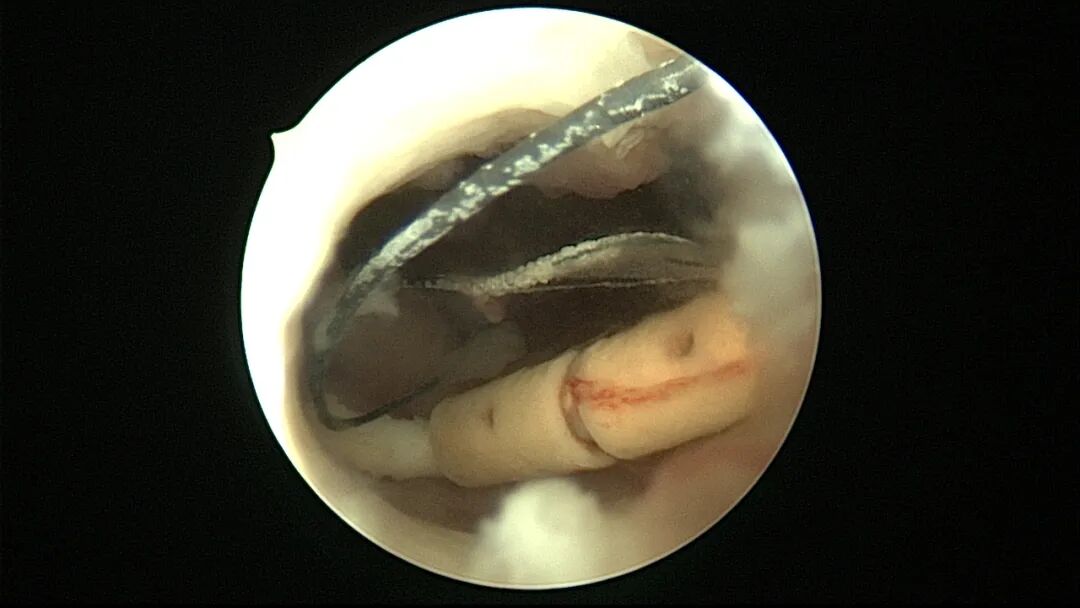

宫腔镜取吉妮环图片

费迎春认为放置吉妮环也有弊端,它放置器是直的,不能任意弯曲定型,即使用手掰弯,松手它还会弹回变直,而且顶端是管状截面,遇阻力不易通过。所以对于前后过度弯曲的子宫可能放置不到宫底,术后复查会出现节育环下移的现象(其实是放置不到位)。吉妮环取出也很困难,保留吉妮环尾丝没有意义,有术者在工作中牵拉尾丝取出吉妮环,90%以上取环失败,大多需要宫腔镜下异物钳取出。